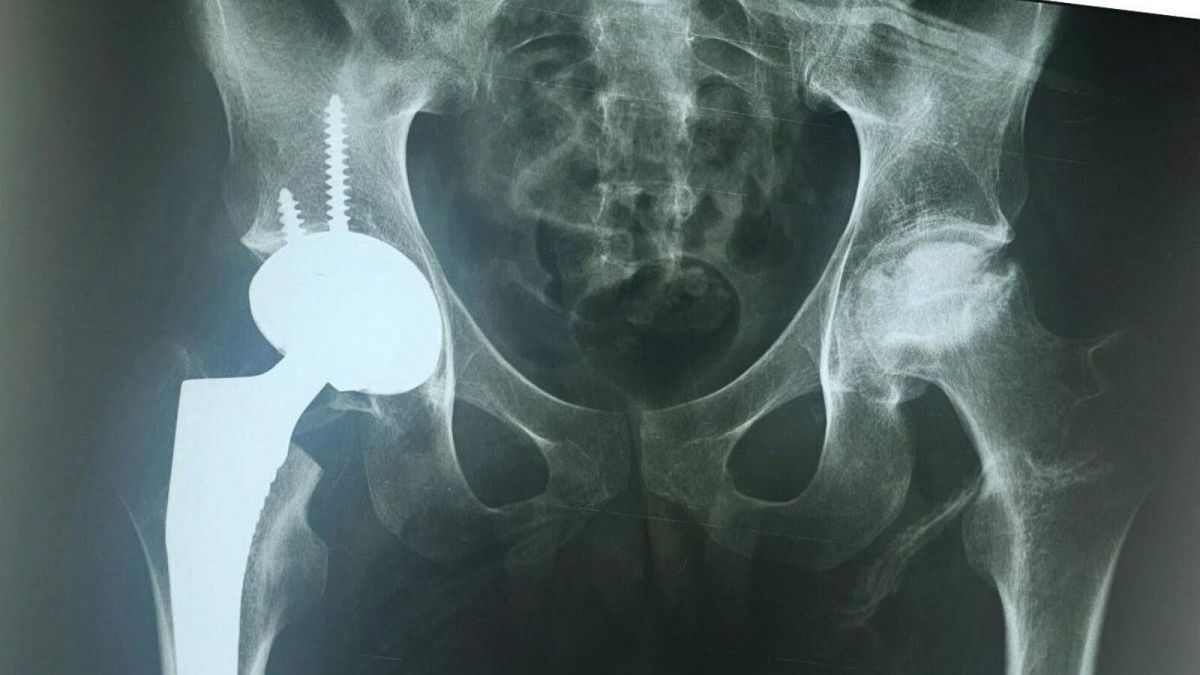

Успешна операција за вградување тотална ендопротеза на колк со керамички компоненти кај 22 годишен пациент во „Св. Еразмо“

Во ЈЗУ Специјализирана болница за ортопедија и трауматологија „Св. Еразмо“ – Охрид успешно опериран 22 годишен пациент кај кого била вградена тотална ендопротеза на десниот колк со керамички компоненти.

Пациентот со дијагноза на акутна лимфоцитна леукемија и претходно подложен на алогена трансплантација на хематопоетски матични клетки пред една година, развил аваскуларна некроза на колковите, која се манифестира со силни болки и ограничено движење.